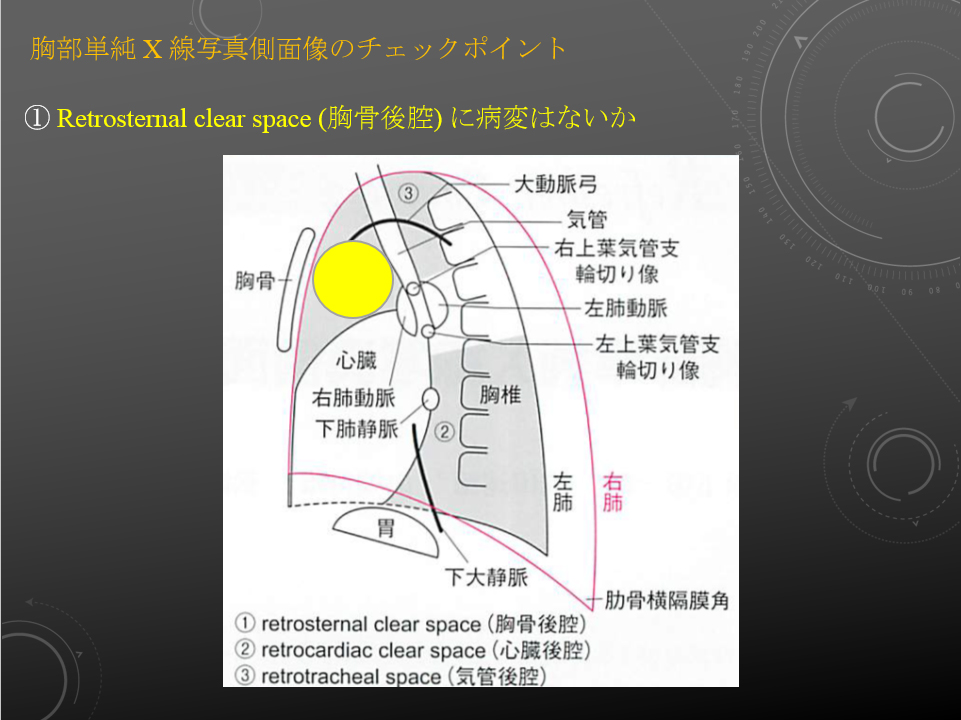

胸部:吸気/呼気、側面

右肺動脈は中間気管支幹の前を横切りながら右下肺野に向かう。

左肺動脈は左主気管支内側を前から後ろに乗りこえ、下方に走行する。

左は右より 1-2cm 高い。

右肺動脈は中間気管支幹の前を横切りながら右下肺野に向かう。

左肺動脈は左主気管支内側を前から後ろに乗りこえ、下方に走行する。

左は右より 1-2cm 高い。